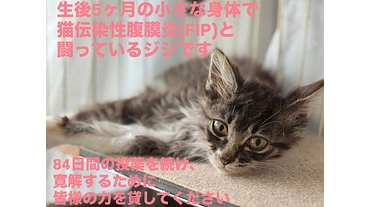

ジジを助けたいです。元野良猫ジジのFIP治療費のお願い。

- 現在

- 510,000円

- 支援者

- 91人

- 残り

- 3日